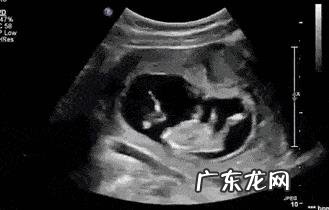

在孕期医生都会通过B超检测胎儿各个器官发育情况 , 以此来判断胎儿发育是否达标 。由于测量手法、角度不同 , 有时候也会出现些许误差 , 但这都属于正常现象 , 而且在医学上允许出现上下两周的误差 。

1、胎儿发育标准:身长约有16cm;

重约110g;

双顶径平均值为3.62±0.58cm;

腹围平均值为10.32±1.92cm ,

【怀孕四个月B超准吗?】股骨长约2.10±0.51cm 。

2、胎儿五官:脸部已经出具人的轮廓和外形 , 在B超显示下 , 看起来更像一个小娃娃了 。眉毛和头发也生长出来了 , 不过量特别稀少 , 孕妈不需要担心 , 等到七个月的时候还会再次发育 。